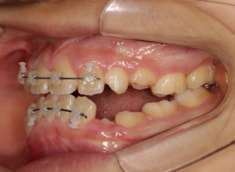

治療開始時

治療開始から11ヶ月